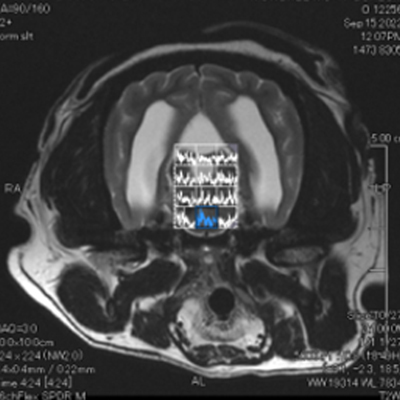

뇌신경·신경근 정밀 평가

신경이 눌리거나 염증이 의심될 때 구조 확인에 도움됩니다.

(참고사진 : 중이·내이 염증으로 8번 뇌신경(청각·균형)에 변화가 보이는 사례)